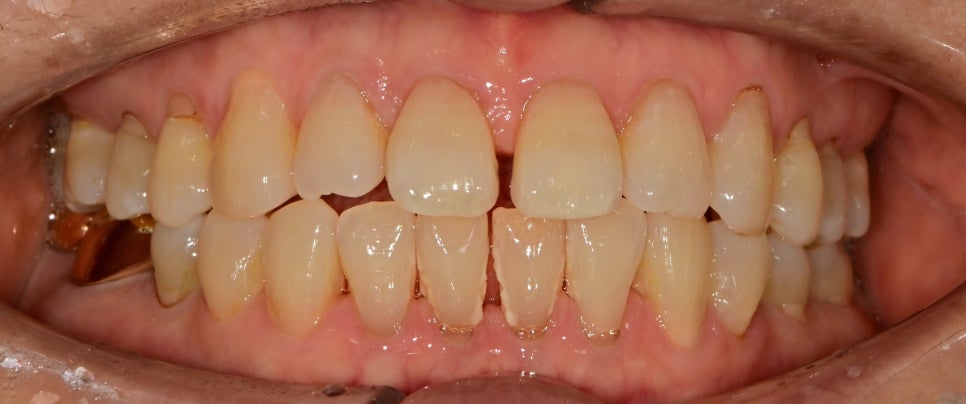

약해진 치주에 의한 치아 벌어짐

초진 사진입니다.

60대의 어머님이셨는데

원래 치아가 살짝 벌어지셨지만

시간이 지남에 따라 치주가 약해져

치아 공간이 더 벌어졌다고 하셨습니다.

벌어진 공간으로 치태관리는 쉽지 않아

치석도 쌓여있는 것이 관찰되었습니다.

환자분께서는 다른 치아의 형태는 괜찮고

가운데 벌어짐 틈만 회복하는 것을 원하셨기 때문에

레진을 이용한 벌어진 공간을 채우는 치료를 했습니다.